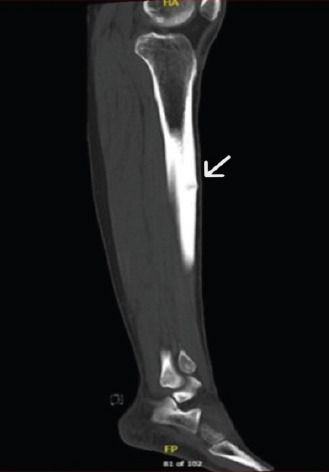

Case report: Here, we discuss a rare clinical case of a sportsman who presented in our hospital. A 26-year-old professional football player presented to us in July 2024 with bilateral leg pain which worsened on playing football. The plain radiograph showed that the middle part of the left side tibial shaft anteriorly had higher density, while the right side was unremarkable; which was further investigated with computed tomography scan on left side on presentation and magnetic resonance imaging on right side on 3 months follow up.